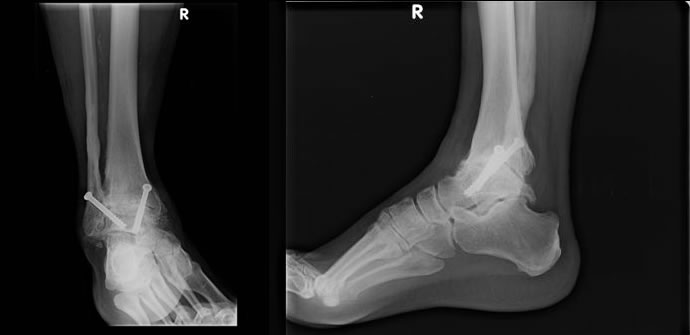

Zur Sicherung der Diagnose reicht meistens die Fussuntersuchung und ein Röntgenbild des OSG. Im Frühstadium bestehen meist eine Druckdolenz im Bereich des oberen Sprunggelenkspaltes, manchmal Reibephänomene (Crepitatio) der chronisch verdickten Gelenksschleimhaut und eventuell eine im Seitenvergleich spürbare Einschränkung der Beweglichkeit. Im fortgeschrittenen Stadium stehen der eigentliche Gelenksschmerz und die Bewegungseinschränkung im Vordergrund. Die effektive Beweglichkeit des OSG muss von der Mitbewegung der Nachbarsgelenke abgegrenzt werden. Das Röntgenbild zeigt eine Verschmälerung des Gelenkspaltes und Knochenwucherungen (Osteophyten).

Durch die Versteifungsoperation (Arthrodese) werden die schmerzhafte Beweglichkeit aufgehoben und so die Schmerzen dauerhaft beseitigt. Auch Achsenfehlstellungen oder Instabilitäten zusammen mit Arthrosen des OSG sind eine gute Indikation für die Arthrodese. Keine andere Operationsmethode vermag das veränderte OSG derart effektiv zu stabilisieren und die Schmerzen so sicher zu reduzieren wie die Arthrodese. Den durch die Versteifung bedingten Verlust an Beweglichkeit vermögen die dem OSG benachbarten Gelenke zum Teil zu kompensieren. Dies kann sich jedoch gelegentlich nachteilig auf diese auswirken und zu vermehrter Abnutzung und Arthroseentwicklung führen. Durch Schuhanpassungen wie Abrollrampe, etc.kann die Gehfähigkeit zusätzlich verbessert werden. Bei geeigneten Patienten kann diese Operation mit nur ganz kleinen Schnitten minimal invasiv, d.h. arthroskopisch durchgeführt werden.

Die Nachbehandlung darf bei beiden Verfahren als etwa identisch bezeichnet werden. Bei gesicherter Wundheilung, d.h. nach drei bis vier Tagen, kann die definitive Stabilisierungshilfe (Stabilstiefel oder Unterschenkelgips) angepasst werden. In der Regel folgt eine vierwöchige Phase ohne Belastung des operierten Fusses. Zeigt das Röntgenbild 4 Wochen postoperativ eine beginnende Überbrückung der Gelenksknochen in eine stabile Arthrodese kann das Gewicht auf den Fuss gesteigert werden. Nach acht Wochen kann meist mit dem Gehen begonnen werden. Auch dieser Schritt braucht eine mehrwöchige Angewöhnung, sodass etwa drei Monate nach der Operation ein flüssiges Abrollen möglich sein wird. Dann ist auch der Zeitpunkt für eventuelle Schuhanpassungen gekommen.